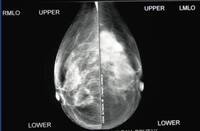

Tubercular mastitis: mammogram showing a mass lesion in the upper outer quadrant

Adapted from the Internet J Surgery (2007); used with permission